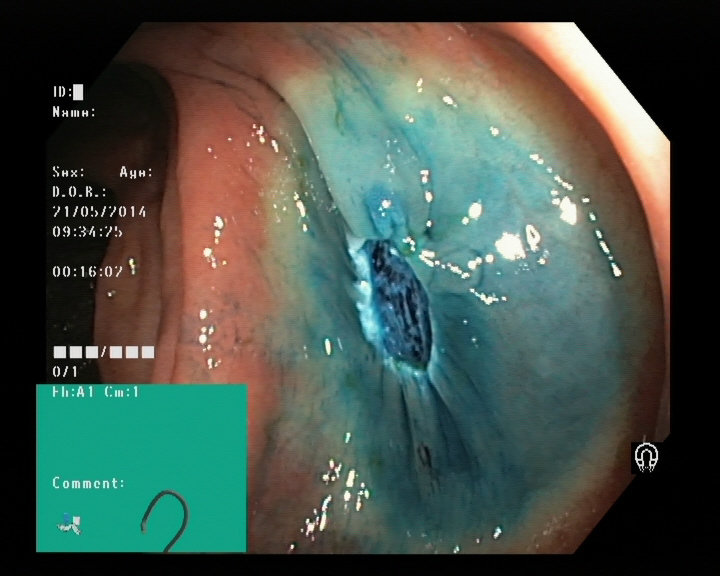

Image of a polyp from a colonoscopy

Gastroscopy and colonoscopy

Dyed lifted polyps

Dyed resection margins